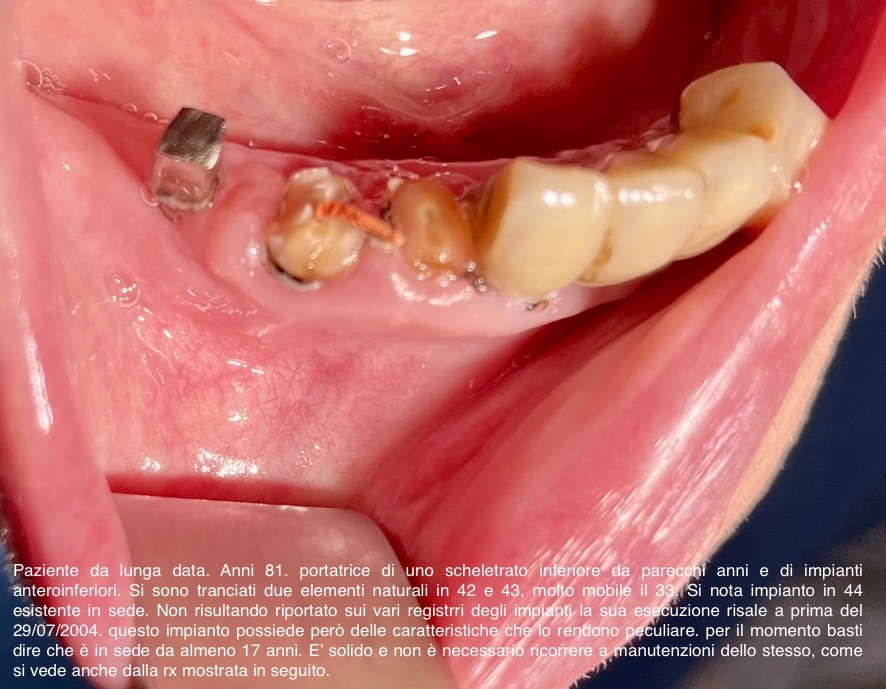

4 - IMPIANTO DI TRAMONTE IN ETA' AVANZATA

Un paziente con impianti italiani da 28 anni ha bisogno ancora di impianti ma ora ha quasi novanta anni e prende molte medicine.